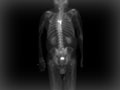

A bone scan is a test that can find damage to the bones, find cancer that has spread to the bones, and watch problems such as infection and trauma to the bones. A bone scan can often find a problem days to months earlier than a regular X-ray test.

During a bone scan, a radioactive substance called a tracer is injected into a vein in your arm. The tracer travels through your bloodstream and into your bones. Then a special camera takes pictures of the tracer in your bones.

Areas that absorb little or no amount of tracer appear as dark or "cold" spots. This could show a lack of blood supply to the bone or certain types of cancer.

Areas of fast bone growth or repair absorb more tracer and show up as bright or "hot" spots in the pictures. Hot spots may point to problems such as arthritis, a tumor, a fracture, or an infection.

You will lie on a table, with a large scanning camera above you. It may move slowly above, below, and around your body, scanning for radiation released by the tracer and producing pictures. The camera does not produce any radiation.